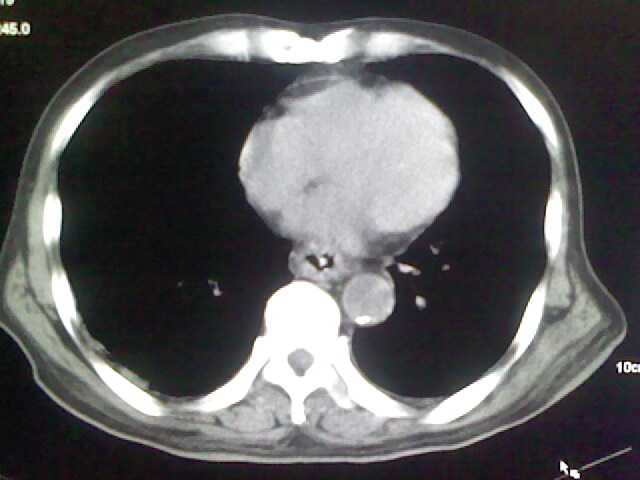

男,70岁,脑出血,长期卧床,左侧背部可触及肿块

考虑右肺及左肺下叶炎症。

右肺及左肺下叶炎症。

考虑右肺及左肺下叶慢性炎症。

肺部感染,背部筋膜增厚,考虑坠积性水肿或炎症

右侧肺部见片状密度增高影,边缘模糊。考虑炎症。另食管壁增厚。

右肺肺气肿并炎症。

肺气肿并炎症。

右肺上叶前段病呈楔形,其尖端指向肺门,考虑肺动脉栓塞可能性大.